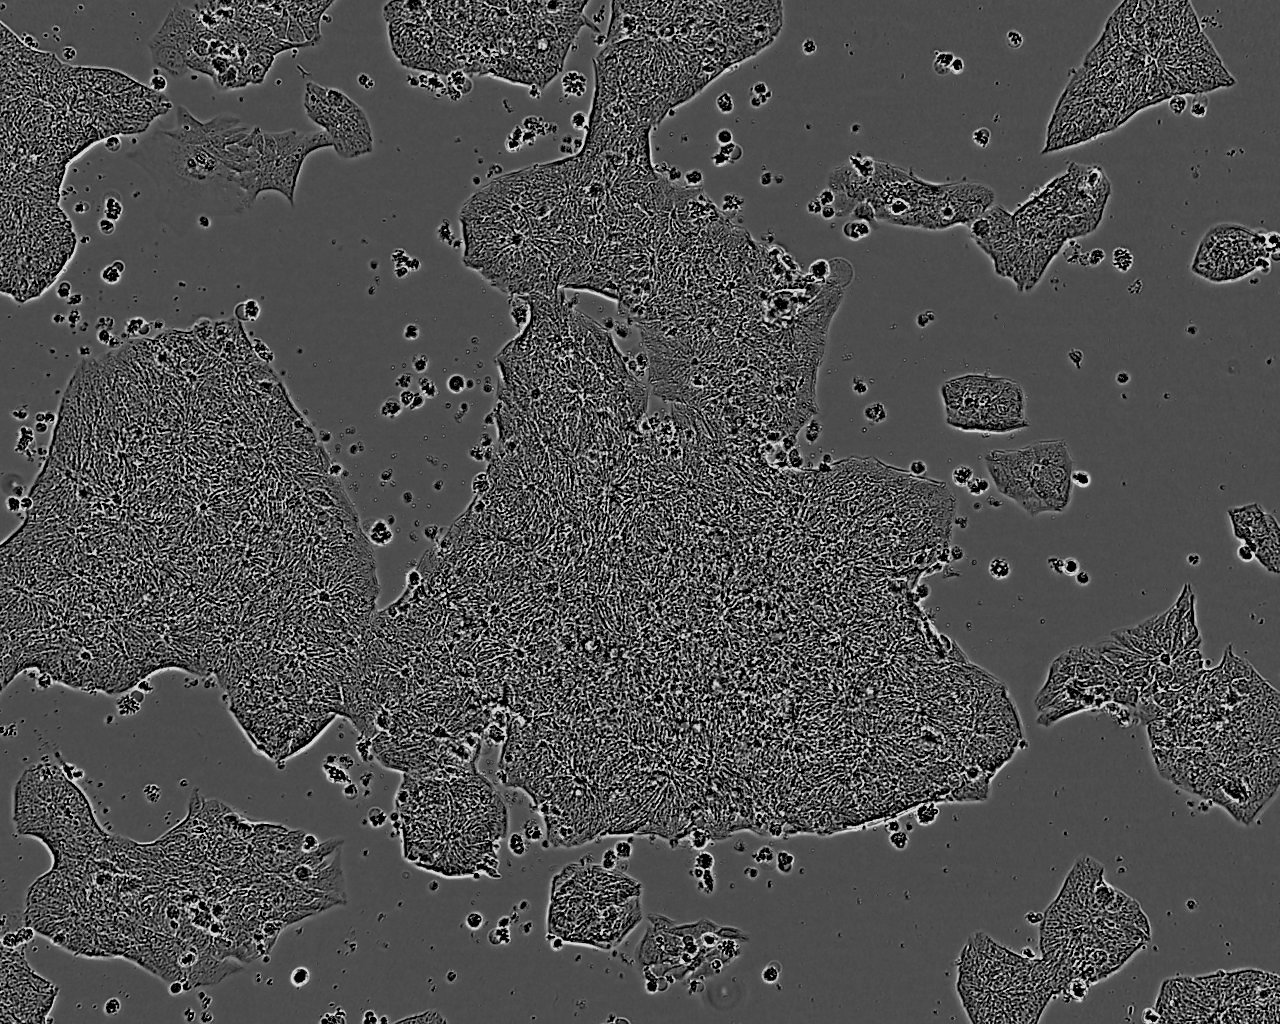

细胞生长:贴壁

细胞形态:上皮细胞样

细胞生长特性:悬浮